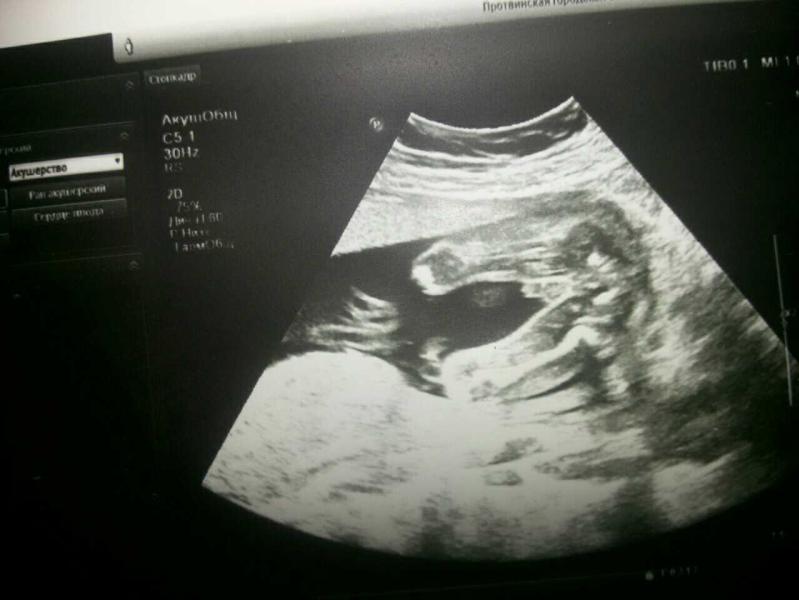

Девчата!!! Помогайте!!! Кто??? Врач сказал, что возможно мальчик. А вдруг это пуповина?. Ааа мы с кумой всю голову сломали!!!

Мальчик) Кокушки торчат)))

Мальчик)